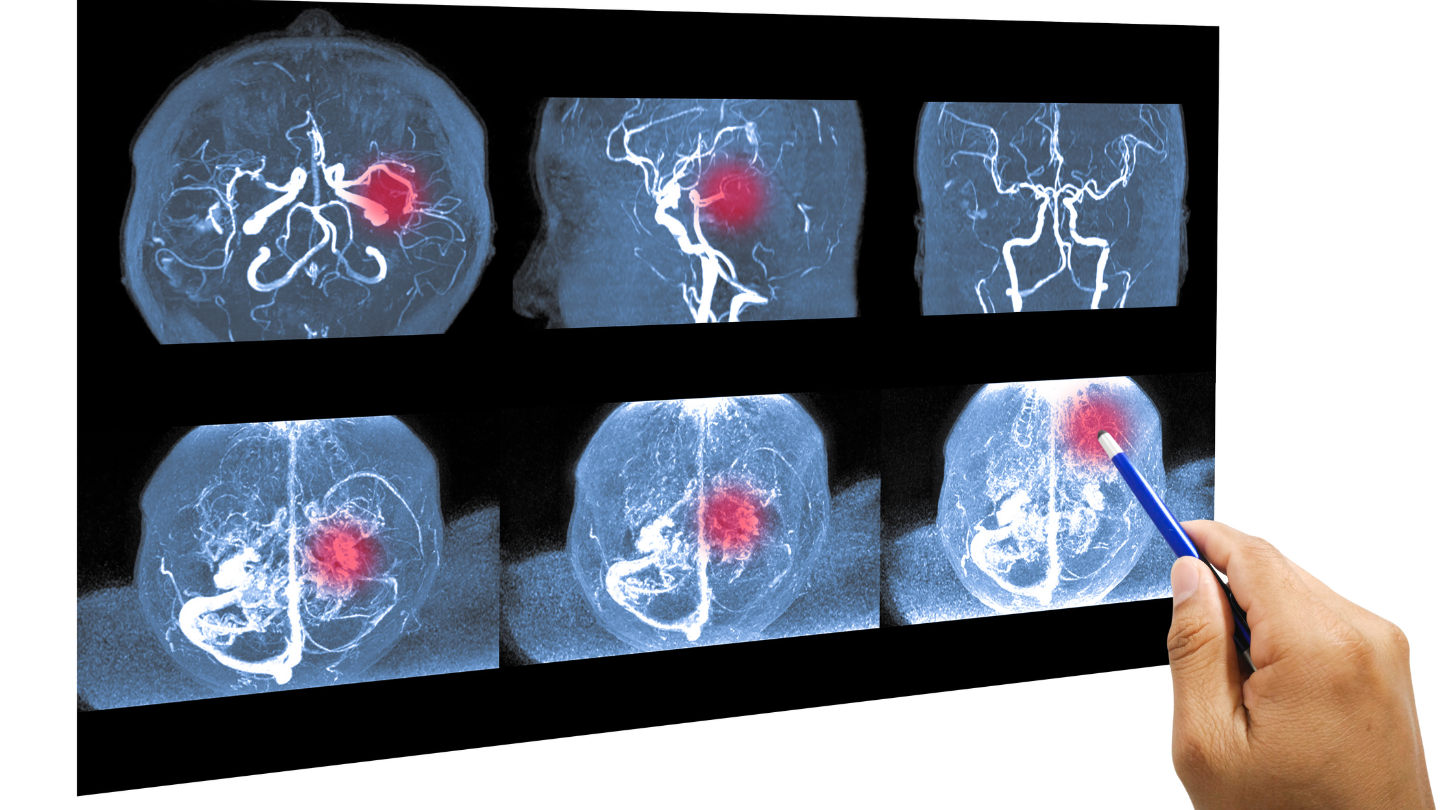

Chụp cộng hưởng từ mạch máu não (MRA)

Chụp cộng hưởng từ mạch máu não (MRA) là một kỹ thuật chẩn đoán hình ảnh hiện đại, sử dụng từ trường và sóng radio để khảo sát hệ thống mạch máu trong não. Phương pháp này giúp bác sĩ quan sát rõ đường đi, kích thước và tình trạng của các mạch máu nuôi não. Trong nhiều trường hợp, MRA không cần tiêm thuốc cản quang, nên khá an toàn; một số tình huống đặc biệt bác sĩ có thể chỉ định tiêm thuốc để hình ảnh rõ hơn.

- Phát hiện: Hẹp trên 50% động mạch cảnh trong sọ, phình mạch, dị dạng mạch, tắc mạch nhỏ.

- Ưu điểm: Cho hình ảnh rất rõ nét, giúp đánh giá chi tiết mạch máu mà không sử dụng tia X, hạn chế ảnh hưởng đến sức khỏe. Ngoài ra, khi chụp MRA, bác sĩ còn có thể quan sát nhu mô não cùng lúc, từ đó đánh giá tổng thể tình trạng não và các tổn thương liên quan.

Nhờ những ưu điểm trên, chụp MRA thường được chỉ định khi người bệnh có các triệu chứng như chóng mặt kéo dài, đau đầu nhiều, yếu liệt, nghi ngờ thiếu máu não hoặc nguy cơ đột quỵ, giúp bác sĩ đưa ra hướng điều trị và theo dõi phù hợp.